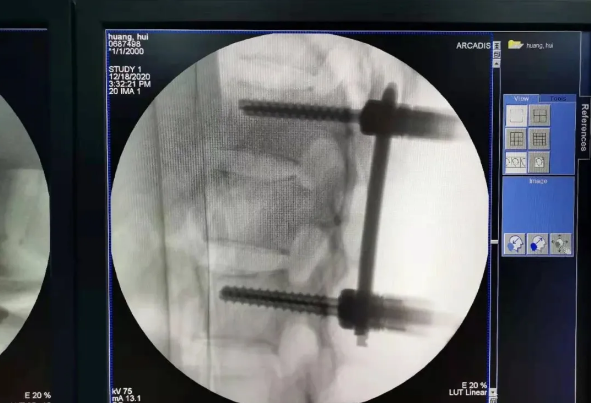

由于天玑?骨科手术机械人的精准及高效,可以使手术时间显着缩短,因此在骨盆骨折手术后,在廖琦教授指导下,脊柱外科团队使用天玑?骨科手术机械人同样为20岁女性腰椎骨折患者“量身定做”最理想、最清静的教科书般的通道,完善清静微创完成手术,手术不但时间缩短,并且出血和透视镌汰。

天玑?骨科手术机械人系统由机械臂主机、光学跟踪系统、主控台车组成,“透视眼”、“稳固手”是它的厉害之处,因此一举解决了骨科手术有三浩劫题:视野差、精准难、不稳固。

? 机械臂就是天玑?骨科手术机械人的“稳固手”,运动无邪、操作稳固,能抵达亚毫米的精度;